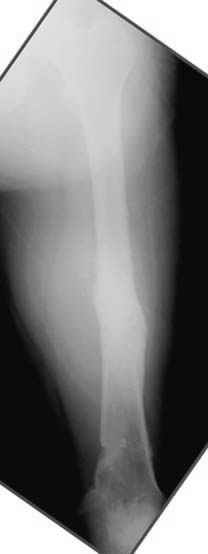

пластическая модель; и коррекция бедра аппаратом Илизарова.

Узкий к-м канал - тонкий гвоздь- усталостный перелом дистальных винтов - развитие нестабильности и как ее результат остеолиз вокруг гвоздя - деформация анатомической оси бедра. Похоже, что я понял почему аппарат, а не новый гвоздь:-)